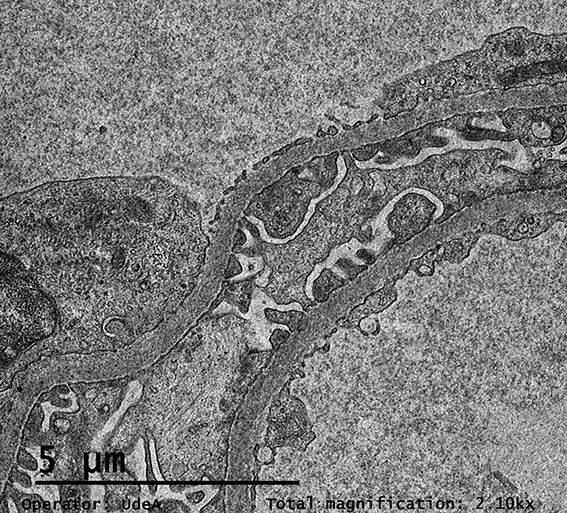

Figura 11. ME, aumento original, X2.100. Procesos podocitarios, membranas basales glomerulares y endotelio normales.

Figura 12. ME, aumento original, X2.100. Paredes capilares glomerulares normales.

Figura 13. ME, aumento original, X2.100.